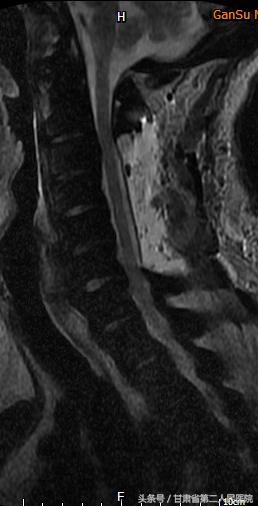

可见后纵韧带骨化

1月25日,省二院骨科袁治国主任、白登彦副主任带领医护团队,在手术麻醉科医护人员的大力配合下,历时5小时,出血不到100ML,顺利完成了“C3-6后路椎板切除钉棒系统内固定术”。

术后,患者麻醉清醒后即感轻松很多。术后2天,患者即能下地行走,好转出院后随访恢复正常。

术后